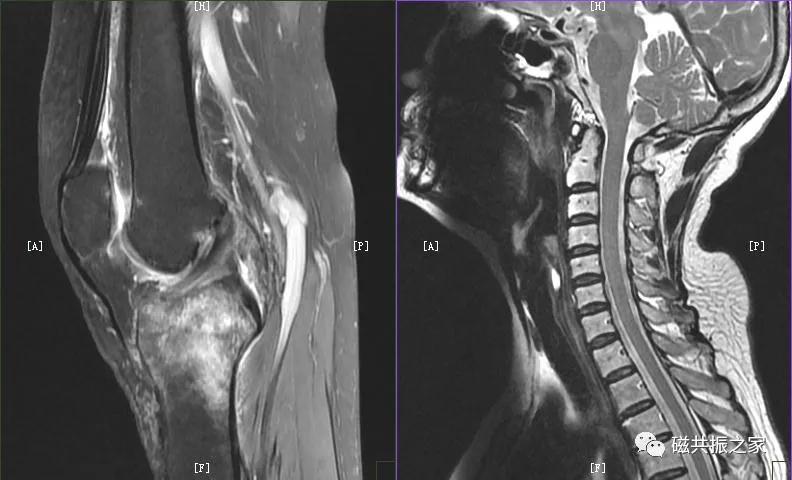

人体很多部位在不同的年龄阶段( 如脊柱、四肢关节等 ) 或特殊时期(如孕期垂体等) MRI信号是具有差异的 。

【相位编码总是在短轴方向?】

书上通常说相位编码方向要放置于短轴方向是因为考虑的是扫描时间。但随着软硬件的提升,扫描时间并不是我们主要考虑的问题,而更需要考虑的是来自相位编码方向上的伪影!

为了减轻相应的伪影,很多部位的相位编码方向是置于扫描部位的长轴方向上的,如关节、脊柱等部位,并且如你细心就会发现几乎所有部位的横轴位DWI的相位编码方向都是前后方向。

所以相位编码方向并不是一定要固定于某一方向,而是要根据扫描的实际情况灵活改变。如上图,要区分到底是不是伪影,改个编码方向即可明确诊断。